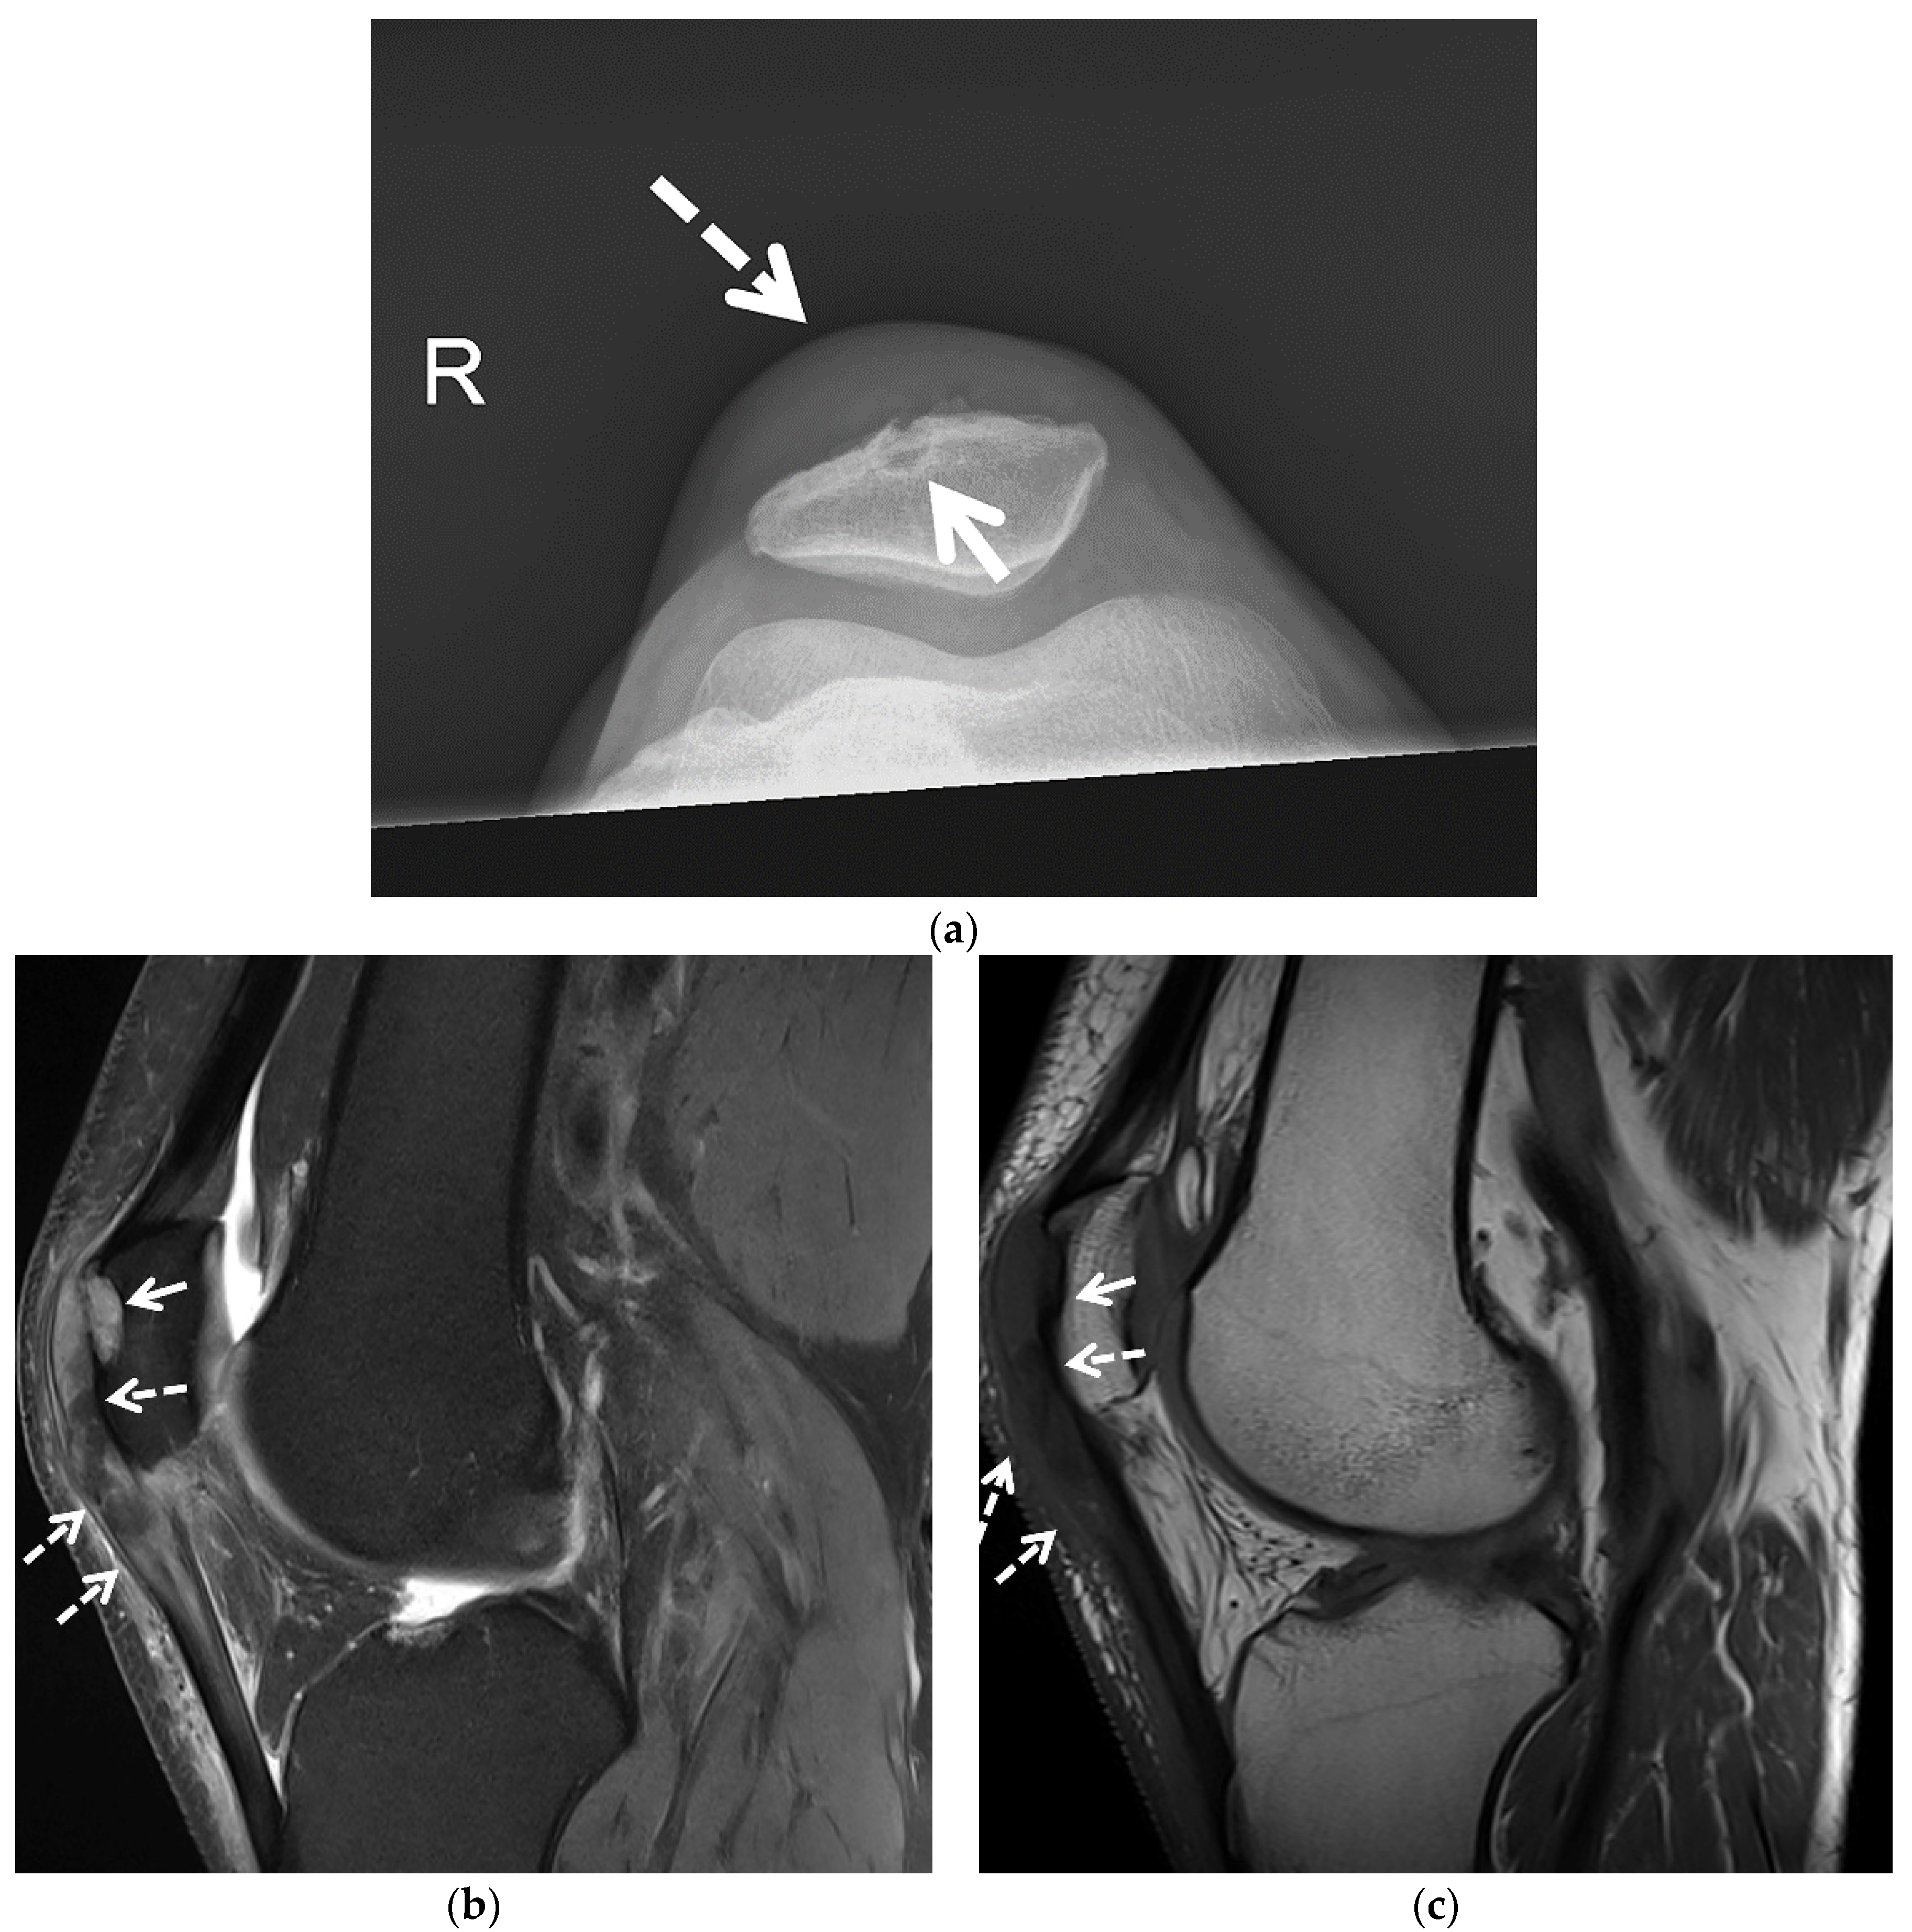

3.1. Radiographs